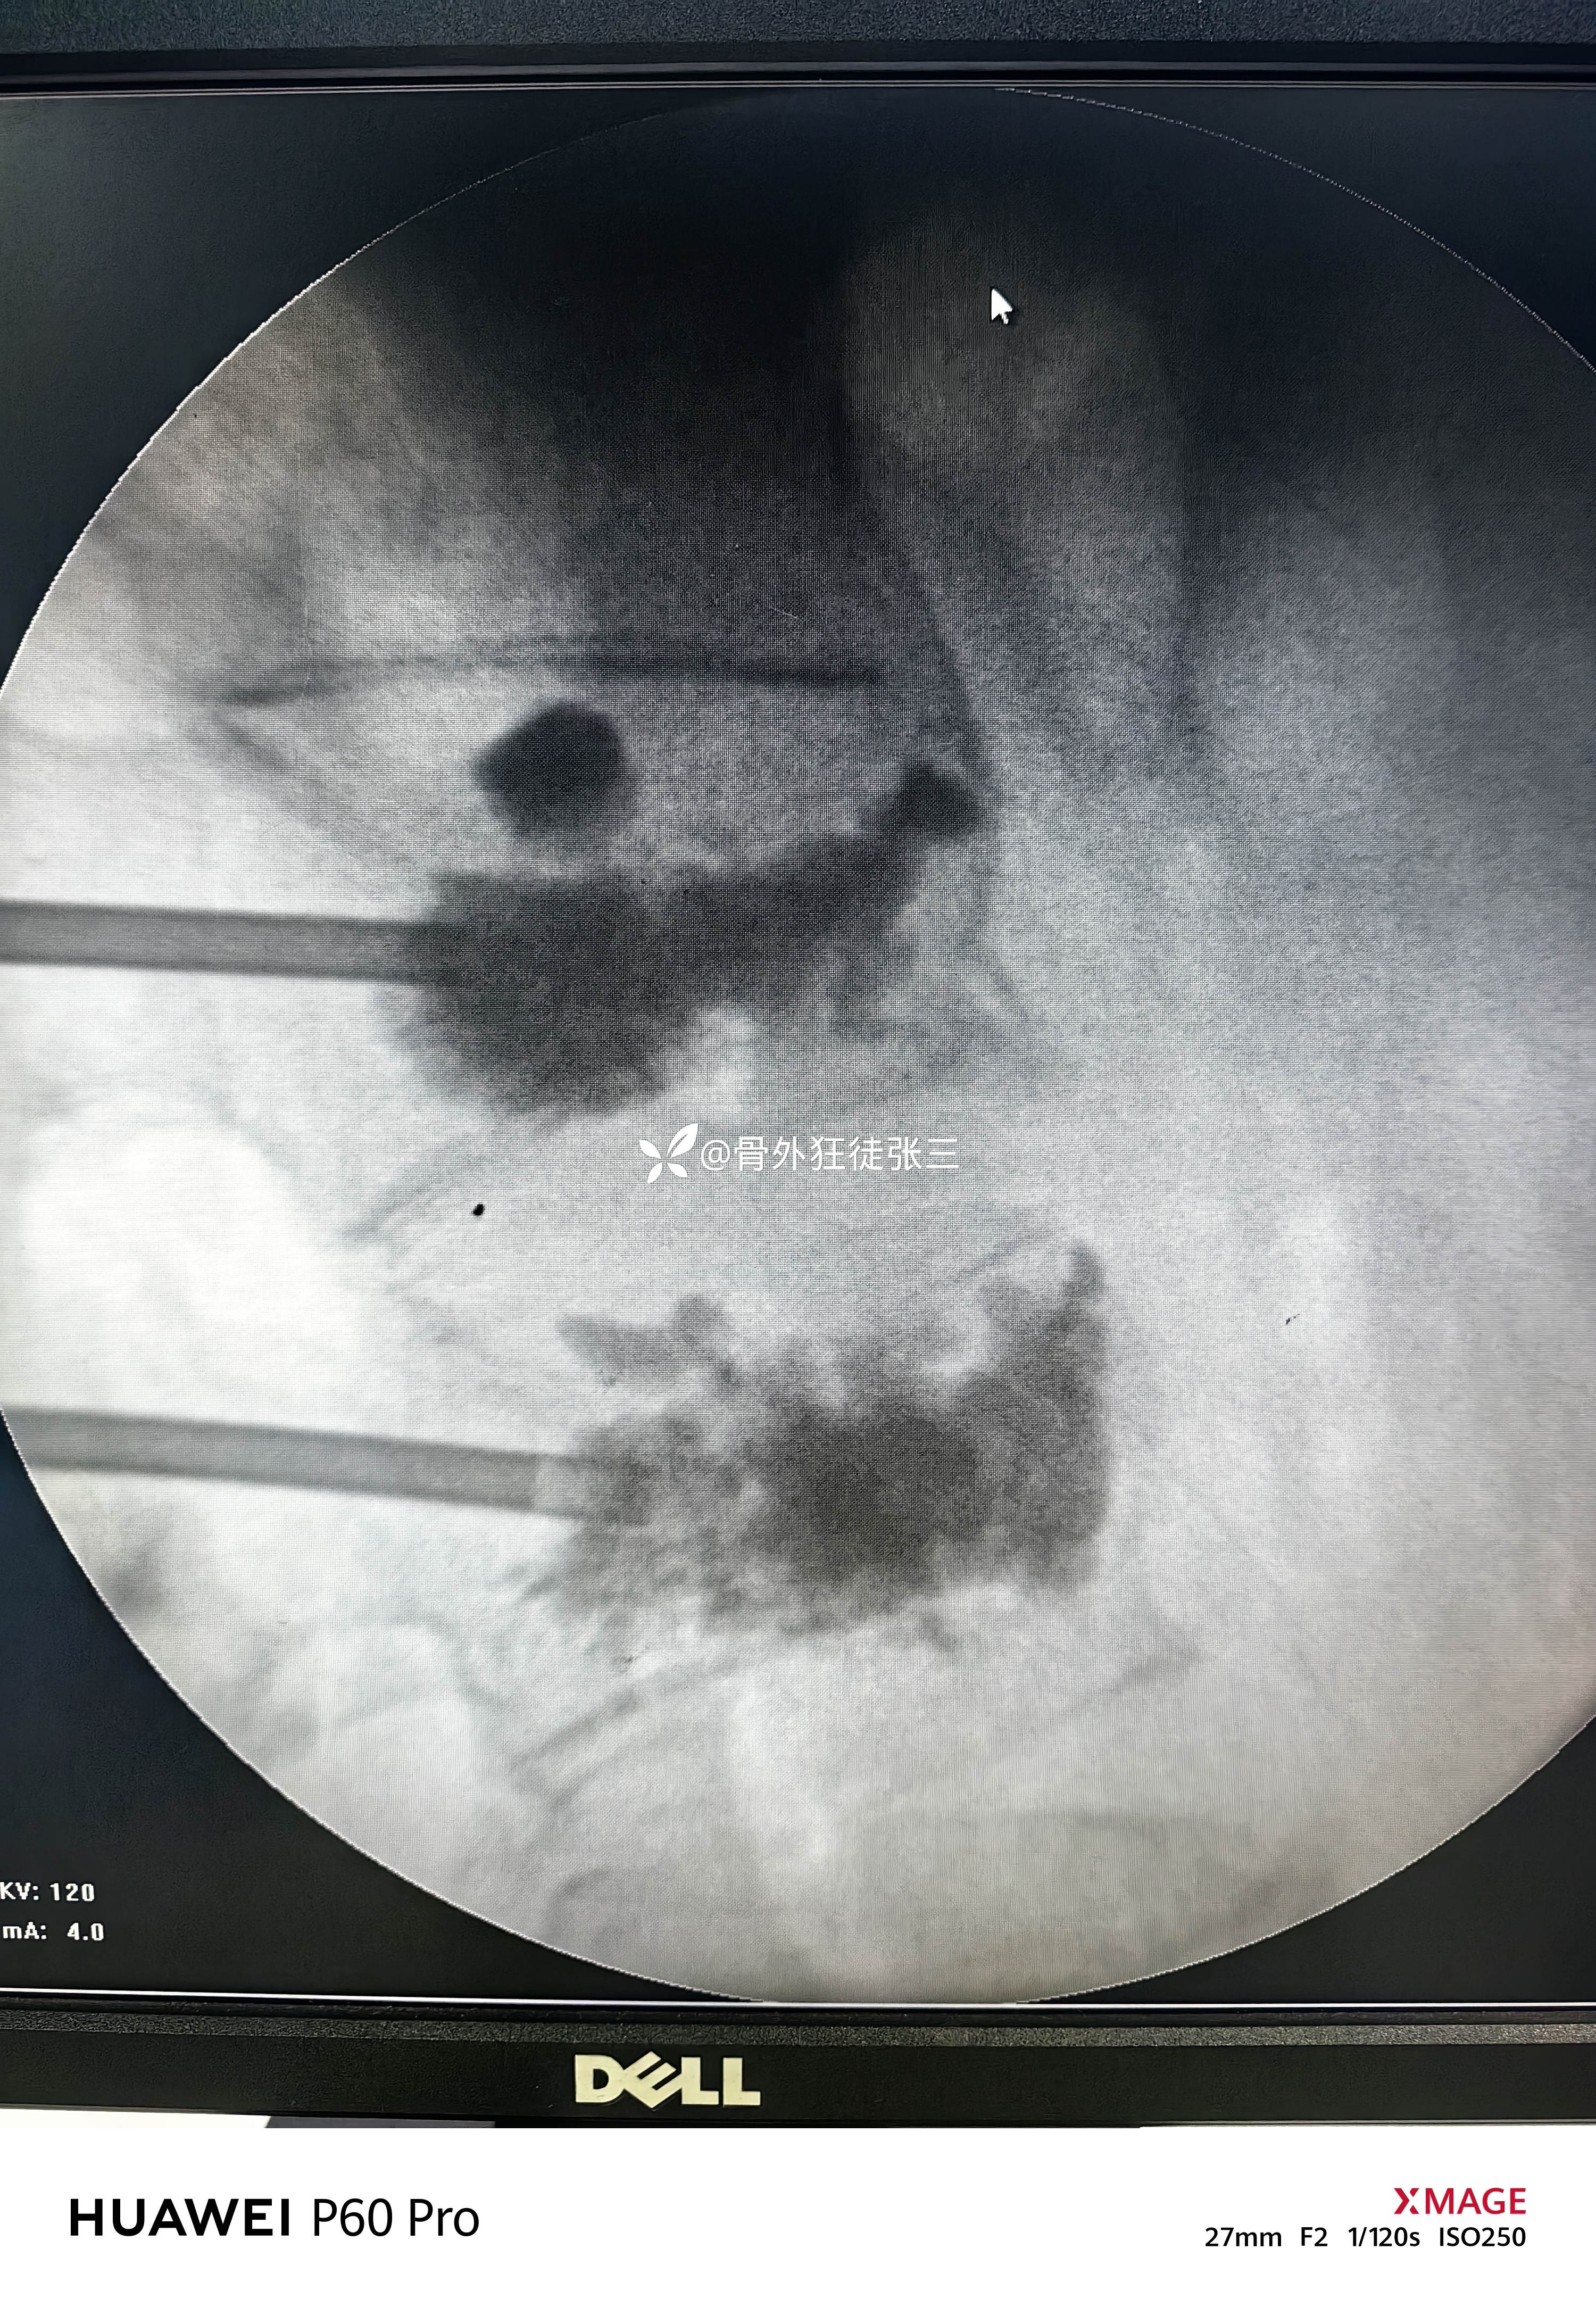

科室术前讨论后

考虑疼痛原因为骨水泥单侧弥散

再次行对侧穿刺,骨水泥置入